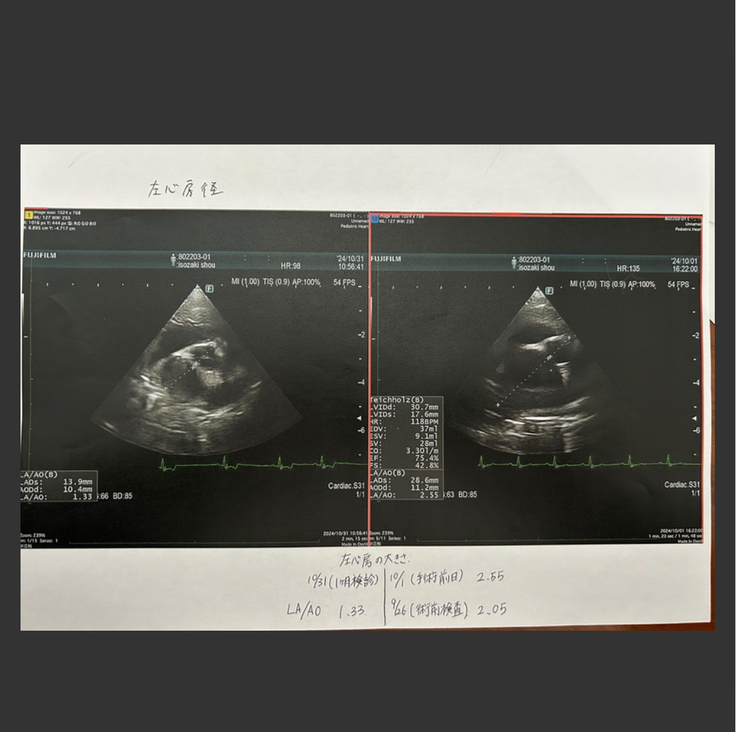

エコー検査で心臓の大きさや逆流値、血栓ができていないかなどをみるそうで、血栓も心臓にできてはいないとのことでした。

三尖便の数値は肺高血圧症と診断される3.0を下回っていました!